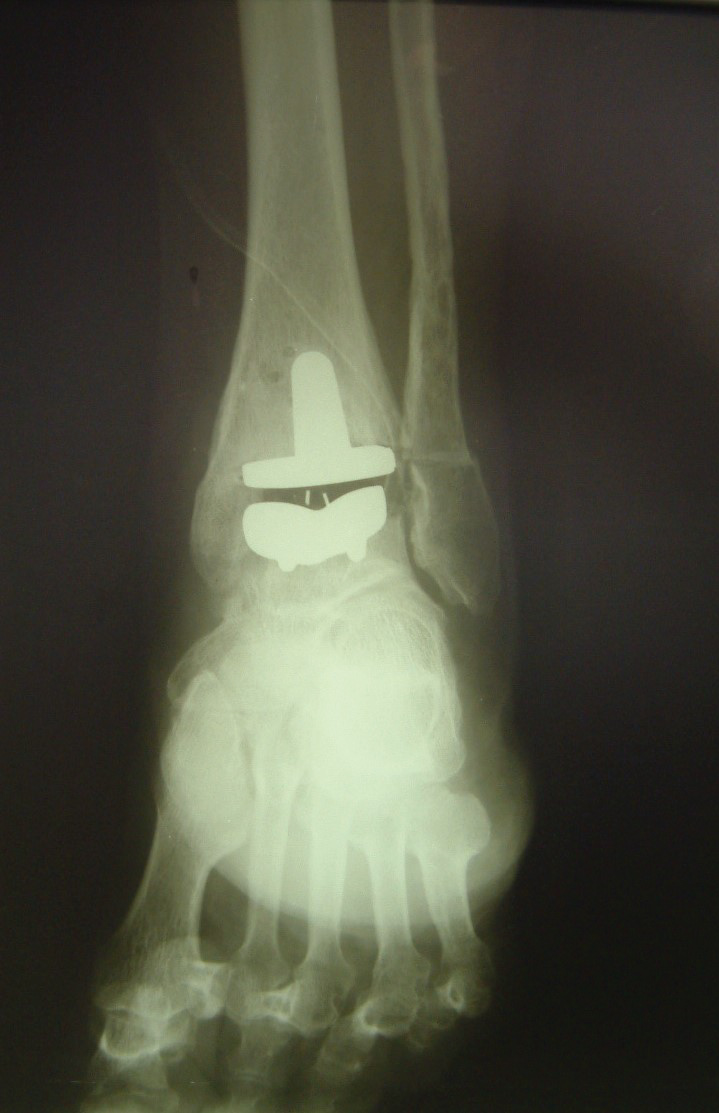

Lucencies were not seen in any of the zones around the talar component. Radiographs showed subsidence of the talar component < 5 mm in 3 ankles and a subsidence between 5 and 10 mm in 2 ankles (Figure 4). None of these 5 patients were associated with a clinical correlation in the radiographic finding. There were no cases of tibial component mobilization and migration. A periprosthetic asymptomatic cyst was detected in 1 patient with posttraumatic arthritis. The cyst was located in the medial zone [14] of the tibial component two years postoperatively (Figure 5). We observed a posterior osteophyte overhanging distally from the tibial plafond in 3 primary osteoarthritis ankles.

Figure 5: Radiographs at the 2-year follow up showing a periprosthetic asymptomatic cyst in the tibial component. No mobilization, no talar component subsidence. A) Maximum plantar flexion; B) Maximum dorsiflexion. View Figure 5